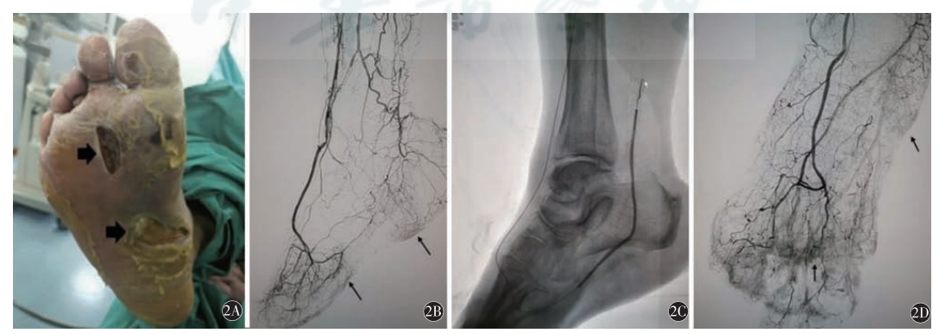

Wound Blush概念提出

2012年,Makoto等人提出足部"创面染色"作为膝下动脉腔内治疗的评价标准。研究显示,获得足部创面良好染色的患者3年保肢率显著提高(96.4% vs 56.8%)。

图:Wound Blush研究资料

Angiographosome理念形成

2018年,Chris Shackles等人正式提出"Angiographosome"理念,强调术中实时造影指导下的靶病变区有效血供重建。该理论体系包括:

图:Angiographosome相关研究

2024年,Patrone教授联合全球180位血管外科专家提出"Woundosome"理念。该理念主张血管重建策略应该直接针对供应肢体缺损或溃疡区域的动脉(包括足背动脉弓和侧支循环),而不仅限于溃疡区域对应的主干动脉。